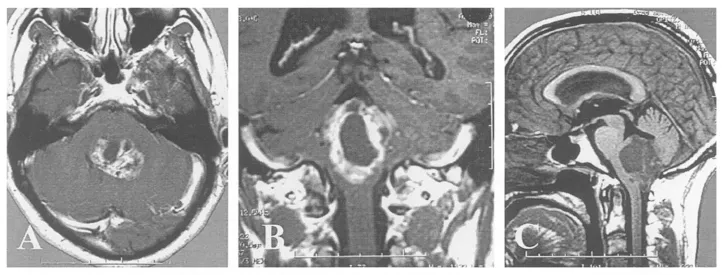

INC生命中枢告急!一名48岁男性在延髓区域发现大型囊实性室管膜瘤,肿瘤呈现藤蔓状生长态势,向上延伸至第四脑室,向下侵入椎管。切除这种位于“生命禁区”的颅颈交界区病变,需要具备深厚的解剖学知识储备。手术面临三大挑战:

视野障碍:肿瘤广泛覆盖神经轴,初次暴露时几乎缺乏操作空间。

血管保护:手术第一步需要在早期辨认并保护为肿瘤供血的小脑后下动脉(PICA)分支。

暴露困难:为充分显露肿瘤顶端,需要精确游离小脑扁桃体并切开后髓帆(本次手术成功避免了小脑蚓部切开)。

巴特朗菲教授首先使用CUSA刀对肿瘤进行减容处理,逐步为关键神经血管结构创造操作空间。随后在显微镜下完成高度精细的肿瘤切除手术:完整游离尾组颅神经根丝、椎动脉(VA)近端及PICA分支。

(A)硬脑膜切开后可见向下延伸至C1水平的大型肿瘤;

尽管肿瘤已侵犯脑干,巴教授仍在第四脑室底部坚持彻底切除,以预防复发,并进行细致止血。研究证据表明,术后CT或MR影像学检查无肿瘤残留是长期生存的有利预后因素。

(E)小脑延髓外侧池内结构保持完整,箭头指示右侧椎动脉;

(D-F)术后6个月MR影像证实肿瘤完全切除。

(F)术后6个月患者临床状态良好。